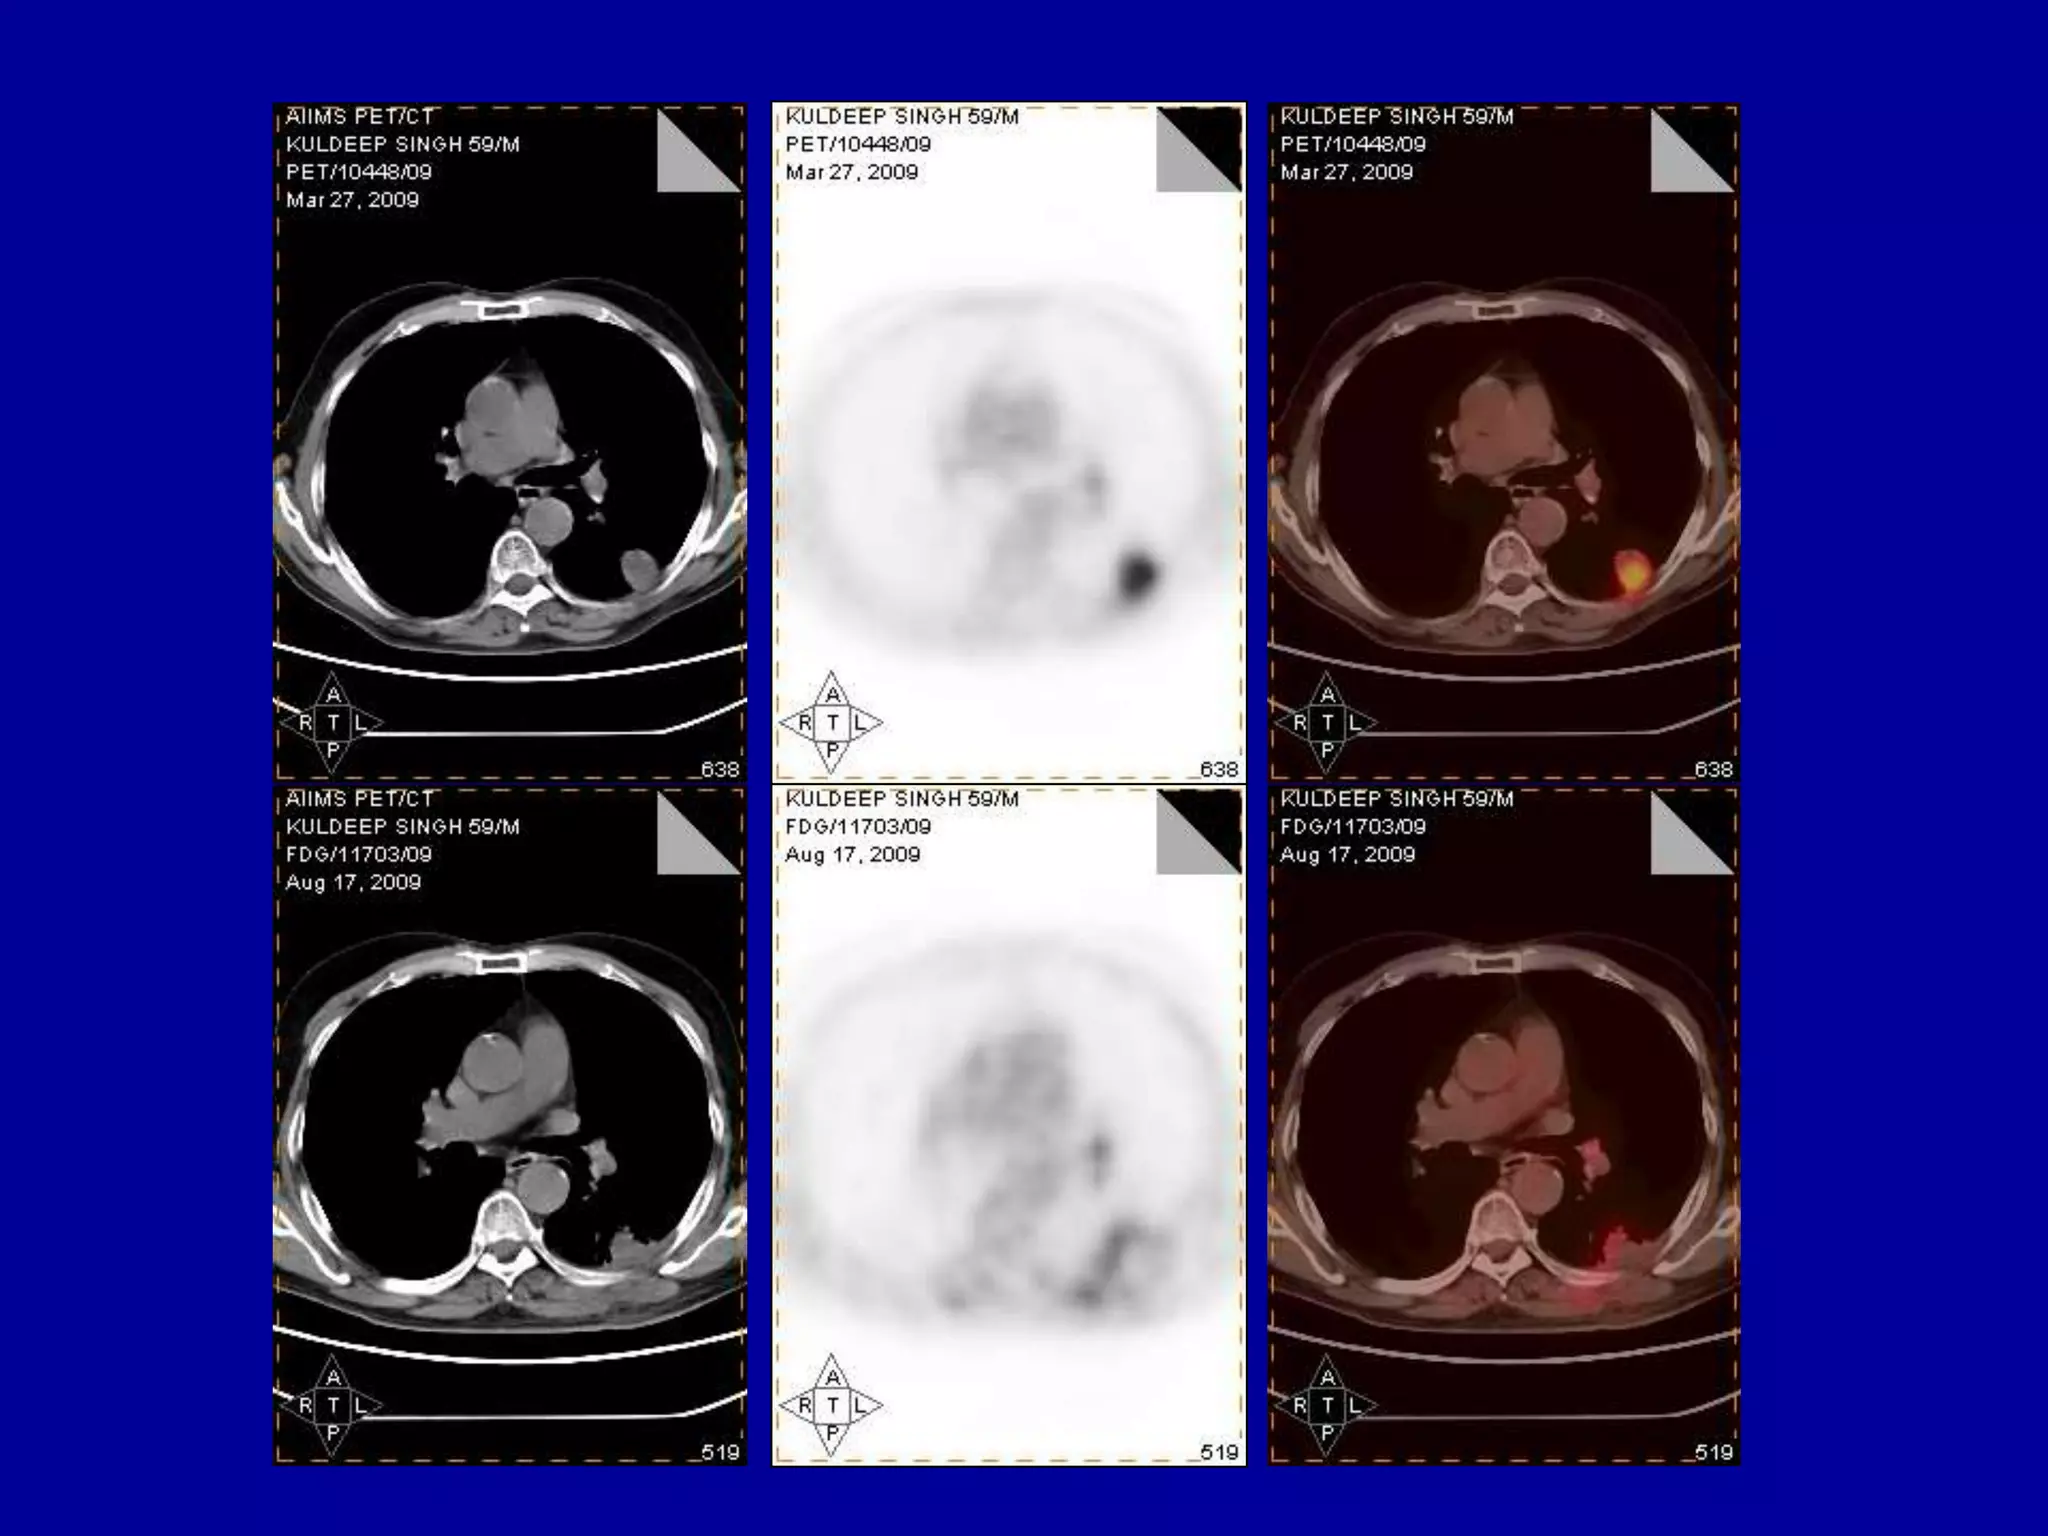

Post implant evaluation-by CT scan